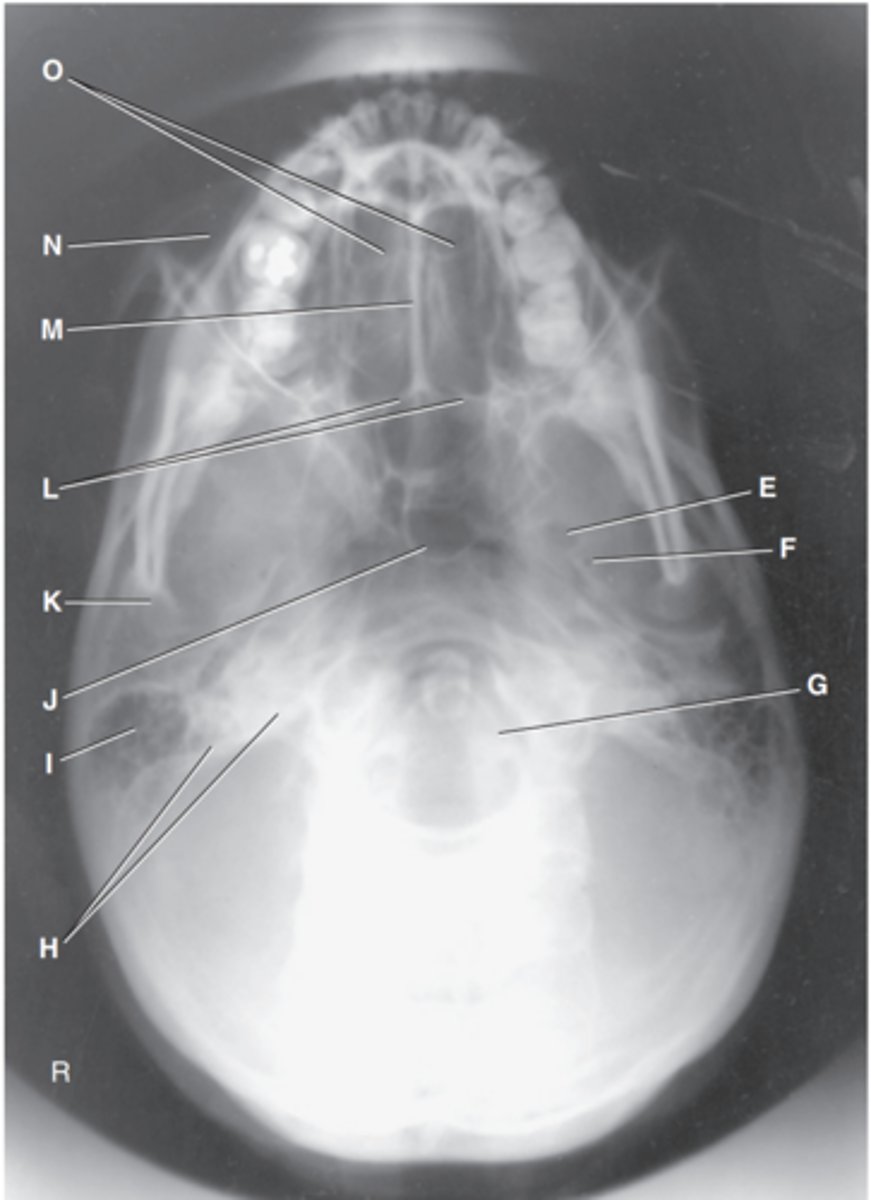

Zygomatic arch

Label A

Right zygomatic bone

Label B

Right nasal bone

Label C

Frontal process of right maxilla

Label D

Anterior nasal spine

Label E

Alveolar process of maxilla

Label F

Alveolar process of mandible

Label G

Mentum or mental protuberance

Label H

Mental foramen

Label I

Body of mandible

Label J

Angle (gonion)

Label K

Ramus of mandible

Label L

Coronoid process

Label M

Mandibular notch

Label N

Neck of mandibular condyle

Label o

Condyle or head of mandible

Label P

EAM

Label Q

TM fossa of temporal bone

Label R

Greater wings of sphenoid

Label S

Lesser wings of sphenoid with anterior clinoid processes

Label T

Ethmoid sinuses between orbits

Label U

Body of maxilla containing maxillary sunuses

Label V